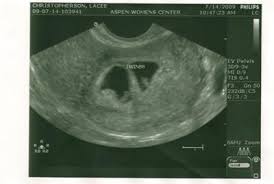

First Ultrasound 6 Weeks 4 Days Life Of Lulu My Story Of Infertility Ivf And Finally Being A Mum And Other Less Intense Stuff

First Ultrasound 6 Weeks 4 Days Life Of Lulu My Story Of Infertility Ivf And Finally Being A Mum And Other Less Intense Stuff from lulujeans.files.wordpress.com

The fetal pole grows at a rate of about 1 mm a day, starting at the 6th week of gestational age. In some women, this bleeding is so light and resolves on its own in a few days; Jetzt timeblock® ganz einfach bei douglas bestellen und 2 gratisproben sichern! After 3 years of trying, we are so excited to be in week 13 with fraternal twins. Thus, a simple and accurate way to date the fetus in an early pregnancy is to add the length of the fetal pole (in mm) to 6 weeks. My husband and i were able to see her. The baby at 4 weeks. A sonographer will only be able.

At six weeks, when it comes to the embryo, things are starting to take shape! The ultrasound image is of twins at 4 weeks. By week 4, the puppies can be felt by palpation. The heart begins to form. Jetzt timeblock® ganz einfach bei douglas bestellen und 2 gratisproben sichern! Along with implantation, comes a rise in the pregnancy hormone hcg. Here are symptoms you will experience. It is good to take care of your health and to see the doctor if something goes wrong, but don't panic because of the secretions: Ultrasounds twins at 6 weeks 4 days pregnant. Six full weeks is when you're 6+0 weeks pregnant. And on a 4 weeks pregnant ultrasound. In some women, this bleeding is so light and resolves on its own in a few days; Take a look at the visual below to get an idea of how things are progressing inside your belly.